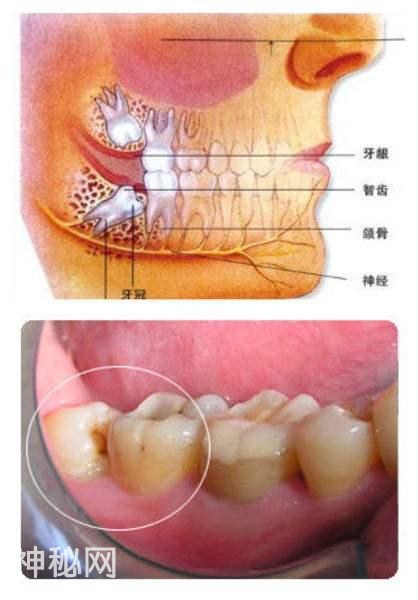

智齿是指人类口腔内牙槽骨上最里面的第三颗磨牙,从正中的门牙往里数刚好是第八颗牙齿。由于它萌出时间很晚,一般在16~25岁间萌出,此时人的生理、心理发育都接近成熟,有“智慧到来”的象征,因此被俗称为“智齿”。智齿生长方面,个体有很大差异,通常情况下应该有上下左右对称的4颗牙,有的少于4颗甚至没有,极少数人会多于4颗。萌出的年龄差异也很大,有的人20岁之前萌出,有人40、50岁才长或者终生不长,这都是正常现象。

牙齿萌出困难称为"阻生齿"或"埋伏牙"。阻生齿最常见于下颌第三磨牙,俗称智齿,此牙萌出年龄在18岁前后,由于萌出前其它牙齿都早已站好队列了,等智齿生长出来时,就会受到其它牙齿的排挤,故而萌出困难,形成了阻生齿或埋伏牙,我们称之为"阻生智齿"。